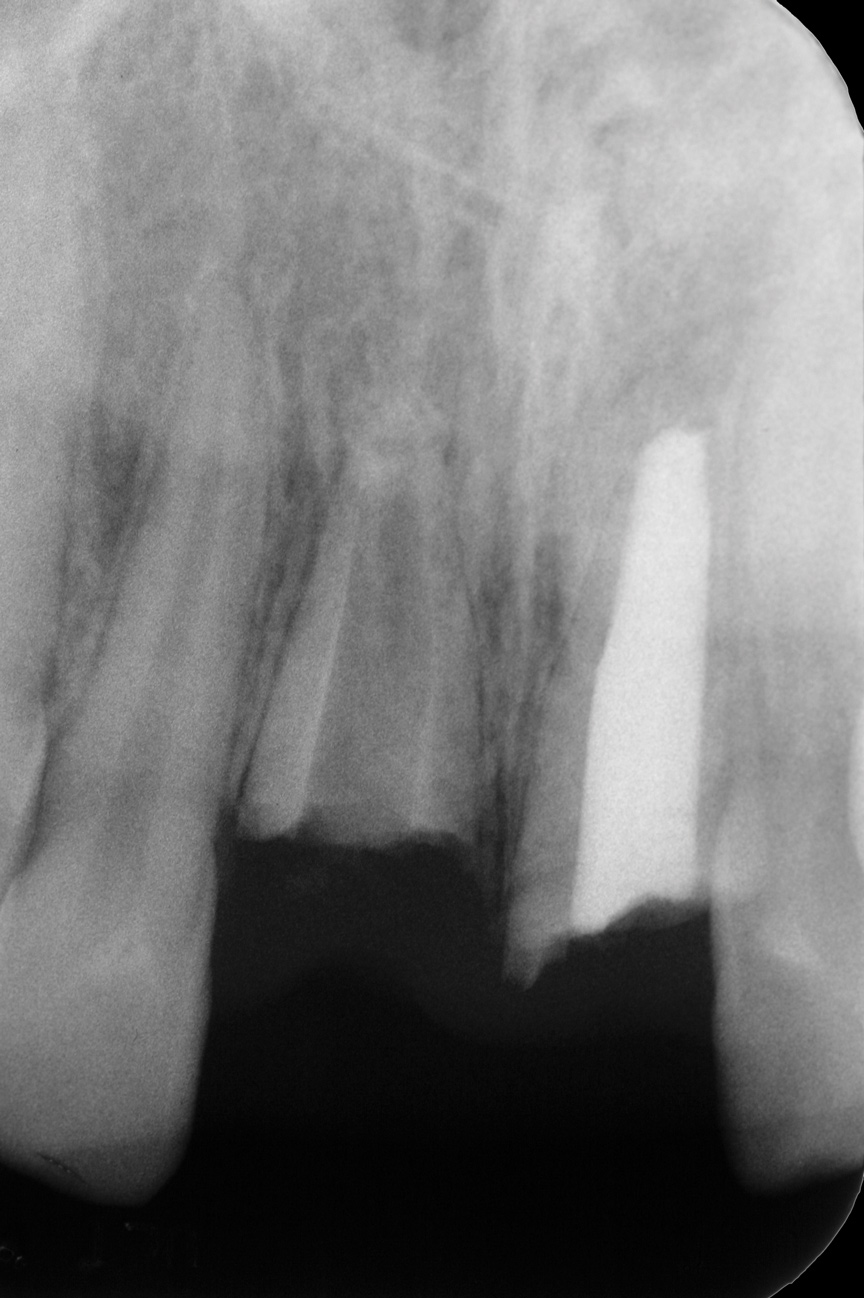

Fig 2. Age 8. Radiograph of teeth Nos. 8 and 9 at initial examination.

Figure 2

The patient's endodontic examination revealed a flexible splint from teeth Nos. 7 through 10 (Figure 1). Tooth No. 8 had a 3 mm x 3 mm class II fracture of the mesioincisal portion of the crown. Tooth No. 9 had a class IV fracture of the crown running labiopalatally from the remaining 2 mm of the crown to bone level on the palatal. A pulpotomy had been performed on the exposed pulp. Both teeth exhibited class III mobility. Teeth Nos. 7 through 10 did not respond to cold testing. None of the teeth were tender to palpation, and only tooth No. 9 had a slight positive response to percussion. Periodontal probings of tooth No. 8 were 4 mm to 5 mm on both the labial and palatal aspects. There was a narrow 12 mm probing on the straight palatal of No. 9; the remaining probing depths were 4 mm to 5 mm.2 A periapical radiograph showed both teeth Nos. 8 and 9 to have incompletely formed roots with wide-open foramina (Figure 2).